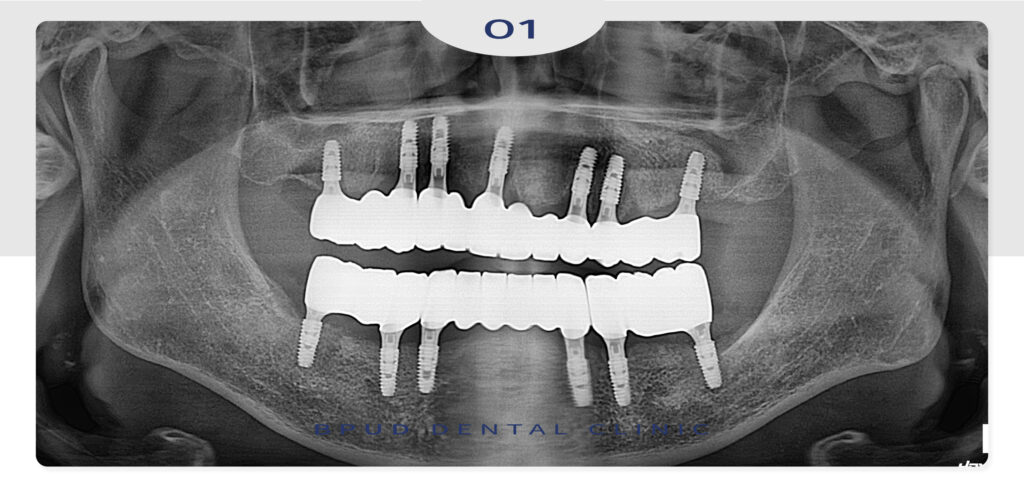

최종 보철물까지 완성한 모습인데요.

환자분께서는 시간 내기도 어렵고

수술을 여러번 받는 것이 힘들 것 같다고 하시며

가능하면 한번에 진행하시는 것을 원하셨고

빠르고 짧은 수술 시간은 환자분의 불편함을

줄여드림과 동시에 통증과 붓기 측면에서도

매우 만족하셨답니다!

더불어 하루만에 수술이 끝나고,

전체적인 치료기간도 짧고 무치악 상태에서

전체 임플란트가 들어가서 만족도가 높으셨습니다.

25.04.07

25.09.11